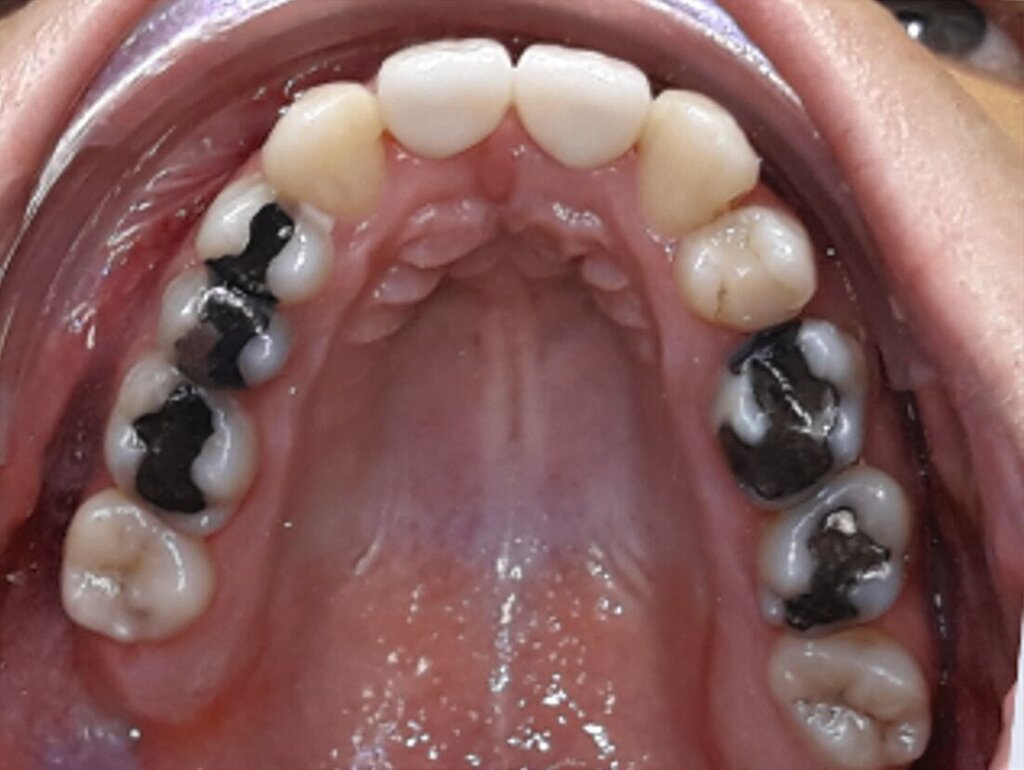

Ein 25-jähriger Patient stellte sich mit dem Wunsch nach Optimierung seines Erscheinungsbildes und seiner Kaufunktion in der kieferorthopädischen Praxis vor (Abbildung 1). Klinisch zeigten sich eine Angle-Klasse-III-Verzahnung mit einer 3/4 Prämolarenbreite Mesialokklusion beidseits und ein zirkulärer Kreuzbiss von 18–12/48–41 und 21–28/31–37. Es lagen ein negativer Overjet von -6,7 mm und ein Overbite von 5,1 mm vor. Eine Mittellinienverschiebung wurde sowohl im Oberkiefer – mit einer Abweichung von 4 mm nach rechts – als auch im Unterkiefer – mit einer Abweichung von 3 mm nach links – diagnostiziert (Abbildungen 2 und 3).

Aufgrund einer hohen Kariesanfälligkeit und einer klinisch floriden Parodontitis waren bereits mehrere Zähne des Patienten extrahiert worden, darunter 16, 11, 25, 38, 35, 45 und 46. Die mesiale Kippung und Aufwanderung der angrenzenden Zähne ließ vermuten, dass der Zahnverlust zeitlich weiter zurücklag. Aufgrund der reduzierten Langzeitprognose des Zahnes 11 entschieden wir uns gemeinsam mit dem Patienten für eine Ausgleichsextraktion des Frontzahns.

Außerdem wurde vor der kieferorthopädischen Intervention die Parodontitis vom Hauszahnarzt behandelt, so dass im Anschluss eine Multiband-Apparatur im Ober- und im Unterkiefer eingesetzt und die Zahnbögen nivelliert werden konnten. Dabei wurden die seitlichen Schneidezähne 12 und 22 anstelle der Zähne 11 und 21 lückig eingeordnet. Die Lücken in Regio 35 und 45 wurden für eine spätere Versorgung vorbereitet.